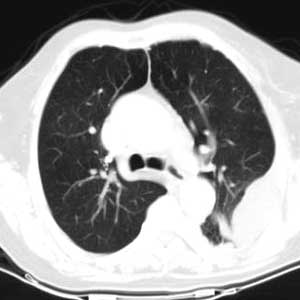

标题: CT0563:病历讨论,胸膜间皮瘤?

测ct值3-6hu,

请上传纵隔窗。目前还是支技包裹性积液(明显梭形),即使是间皮瘤并积液也少梭形的。

从图片看,包裹性积液好象更合理,梭形,ct值3-5hu(在哪看到的?);胸膜间皮瘤如此规则,不多见。

左侧背部胸膜肥厚,伴包裹性积液,不考虑间皮瘤.